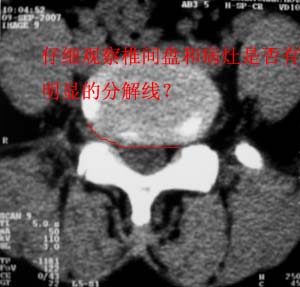

对比观察

[emb10]为什么说是椎间盘病变呢?还有椎间盘脱出有脱向头端方向的吗?